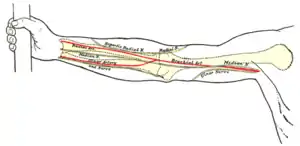

Upper limb

- Brachial pulse: located on the inside of the upper arm near the elbow, frequently used in place of carotid pulse in infants (brachial artery)

- Radial pulse: located on the lateral of the wrist (radial artery). It can also be found in the anatomical snuff box.

- Ulnar pulse: located on the medial of the wrist (ulnar artery).